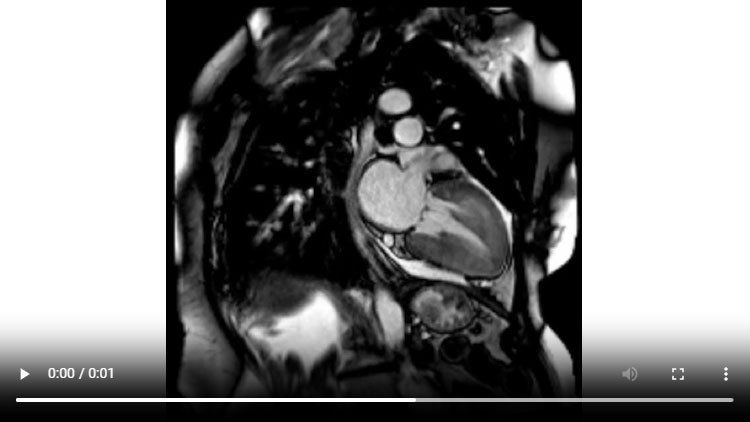

Figure 1D : Séquence Ciné-IRM - Coupes 2-cavités

- Présence d’une hypertrophie ventriculaire gauche (HVG) asymétrique à prédominance septale mesurée au maximum à 23 mm.

- Visualisation de la sonde de PM avec artéfacts métalliques modérés au niveau du ventricule droit (flèches roses).

- Présence d’un épanchement péricardique de moyenne abondance (flèches rouges).